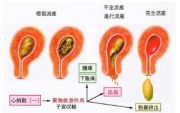

| 2021年7月26日 (一) 20:01 | 流产.jpg (文件) |  |

14 KB | 77921020 | Uploaded with SimpleBatchUpload | 3 |